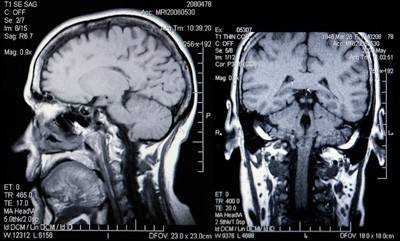

Снимок МРТ головного мозга в двух проекциях

МРТ гипофиза при краниофарингиоме: сканы в разных проекциях